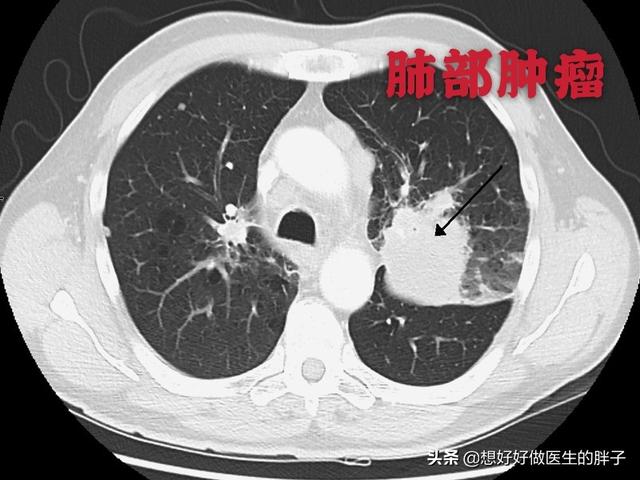

Dieser unregelmäßige Knoten in der linken Lunge ist der Primärherd, der nur 2,6 cm groß ist. Lungenkrebs mit Knochenmetastasen wie diesem ist nicht mehr operabel. Man kann ihm nicht helfen, Lungenkrebs ist zu häufig und einige der frühen Symptome sind atypisch oder sogar symptomlos.Bei etwa 30 % der Lungenkrebse sind Symptome von Metastasen die erste Manifestation, und Metastasen werden zuerst entdeckt, bevor weiterer Lungenkrebs entdeckt wird.

Es handelte sich um eine pathologische Fraktur, die durch geringe äußere Kräfte auf der Grundlage einer Knochenmetastase verursacht wurde. Es wurde eine Punktion durchgeführt und die Pathologie war eine Knochenmetastase eines schlecht differenzierten Lungenadenokarzinoms.

Was sind die Symptome, die bei Knochenmetastasen auftreten können? Das erste Symptom ist der Schmerz. An der Stelle der Knochenmetastase treten aufgrund der Zerstörung des Knochens Schmerzen auf, die anfangs vielleicht keine offensichtlichen Symptome oder intermittierende Schmerzen haben, aber da der Tumor den normalen Knochen fortschreitend zerstört und sich allmählich verschlimmert, werden auch die Schmerzen an der metastatischen Stelle allmählich stärker. Klinisch gesehen kann es vorkommen, dass wir einen Fall von Knochenschmerzen an einer bestimmten Stelle des Körpers vorfinden, der auf eine Knochenmetastase eines bösartigen Tumors zurückzuführen ist. Vor einiger Zeit traf ich einen Fall, 40 Jahre alt, Schulterschmerzen, dachte, Schultersteife, rieb ein paar Tage der medizinischen Öl nicht sehen Verbesserung, aber mehr und mehr Schmerzen, so ins Krankenhaus zur Untersuchung, hat eine Magnetresonanztomographie, Schulterblatt wurde von einem Stück (Tumor) gegessen, unter Berücksichtigung Knochenmetastasen, und dann hat eine Brust-CT, ein Knoten in der rechten Lunge, und nahm dann eine Biopsie, um die Pathologie, die Knochenmetastasen von Lungenkrebs zu tun war. Die Informationen sind wie folgt.